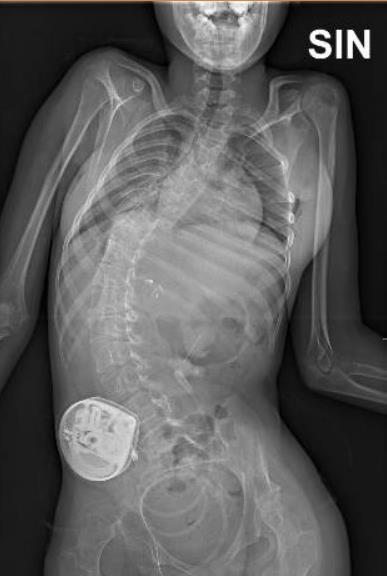

Functional mobility level and baseline gait quality are both important factors to predict gait outcomes after SDR. If candidates are well selected, SDR can be a successful intervention to improve gait both in children with spastic diplegia.